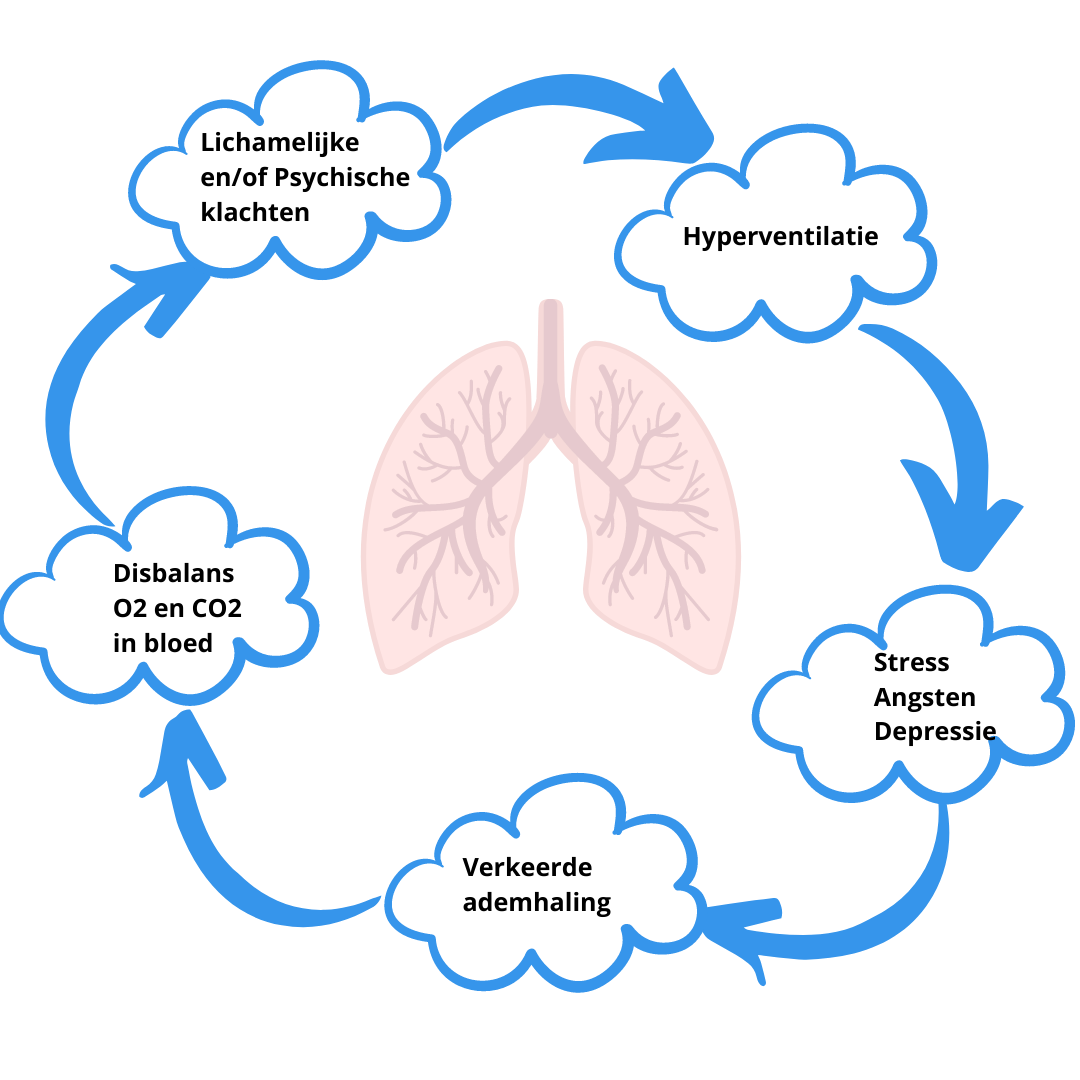

Neem nu stress als voorbeeld. Bij stress zal je vaak (onbewust) sneller gaan ademhalen. Op dat moment veranderd de verhouding zuurstof en koolstofdioxide in het bloed. Als je dat lang genoeg blijft doen, dan zijn er organen in ons lichaam die daaronder te lijden hebben. Dat kan op zijn beurt het gevoel van duizeligheid en hartkloppingen geven, en dus een extra stress prikkel. Met als gevolg dat je nog sneller gaat ademen en er een vicieuze cirkel ontstaat. Op dat moment ben je dus aan het hyperventileren.